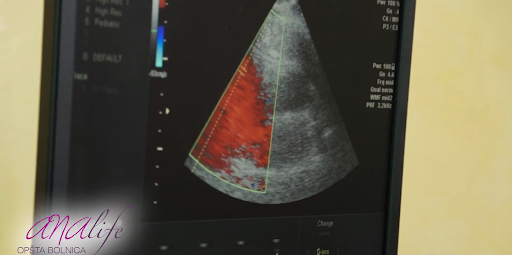

Uzimajući u obzir širok spektar bolesti koje daju isti simptom-zamaranje, neophodno je obaviti internistički i kardiološki pregled radi utvrđivanja uzroka tegoba. Dodatne metode koje nam omogućavaju postavljanje tačne dijagnoze su analize krvi ( vrstu analize indikuje kardiolog nakon obavljenog kliničkog pregleda), ultrazvučni pregled srca, radiografija srca i pluća. Dijagnostički pristup se određuje individualno za svakog pacijenta.